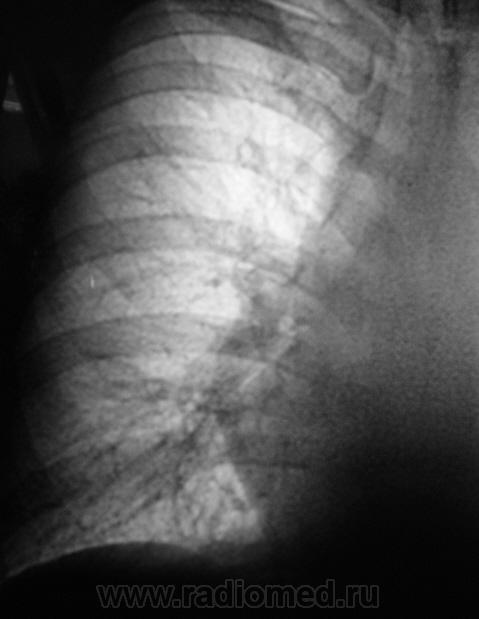

2 срез.